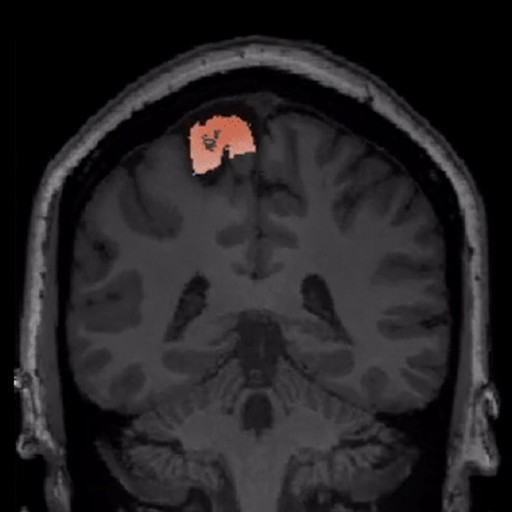

Diagnostics. AI-powered lesion identification combined with expert radiologist validation delivers comprehensive case reports

BrainScores was built specifically for epilepsy surgery. Generic neuroimaging platforms serve multiple conditions but lack the depth required for focal cortical dysplasia detection

BrainScores was built exclusively for epilepsy surgery. Generic neuroimaging platforms serve multiple conditions but lack the depth required for focal cortical dysplasia detection.